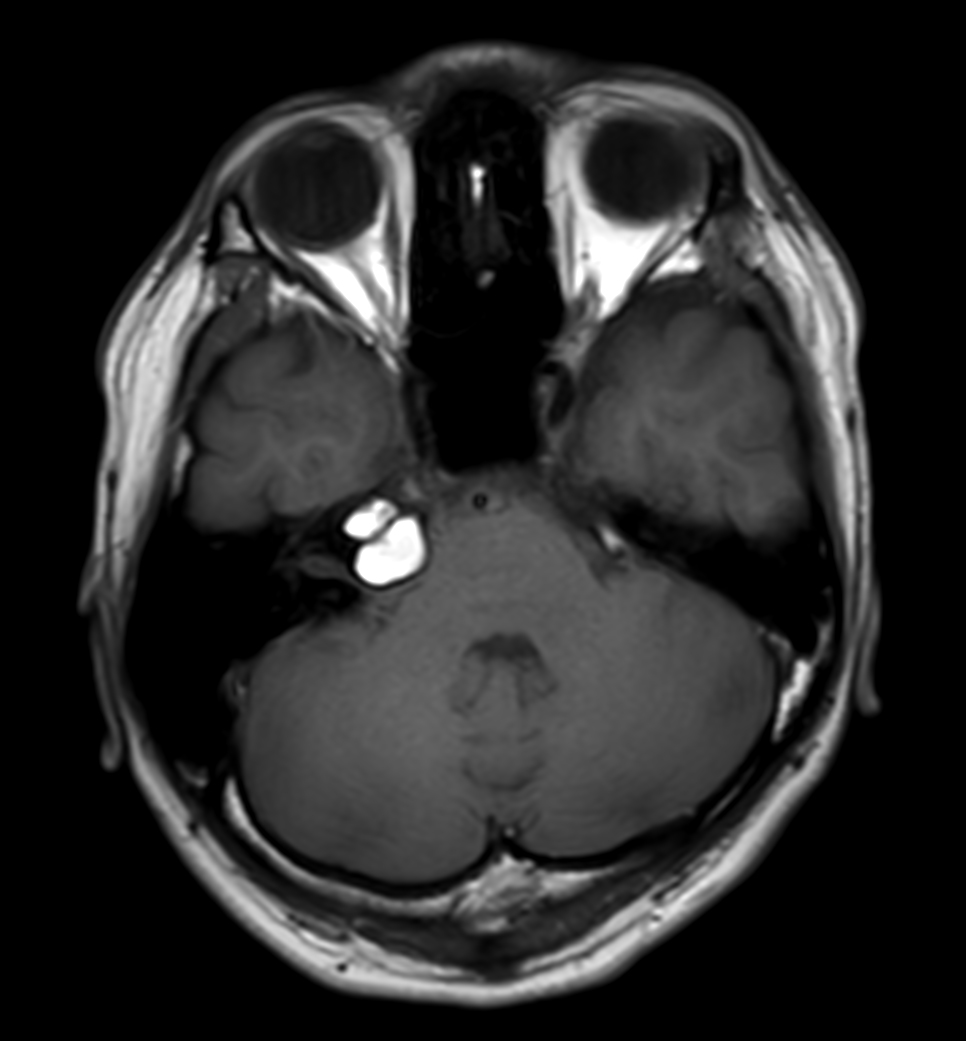

Patient with an IAC lesion. Comparing different DWI methods (EPI, TSE, ZOOM). Compressed SENSE is added to all TSE sequences to decrease scan times, thereby shortening the time the patient has to spent in the magnet. The dS Head 32ch coil is used to enhance image quality.

T1w SE